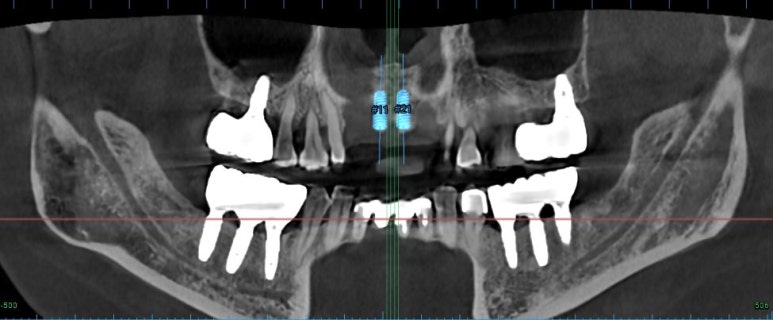

엑스레이를 보시면, 양쪽 위턱 가쪽 앞니가 거의 잇몸뼈와 분리되어 둥둥 떠있는 모습을 보실 수 있습니다.

잘 모르시겠다면, 제가 표시해드리겠습니다..!!

점선이 실제 잇몸뼈의 높이를 나타내고 있습니다.

노란 화살표로 표시한 두개의 위턱 측절치가 남아있는 뼈 없이 둥둥 떠있는 모양이에요.

axial view를 보시면, #12,22 부위에 정말로 엄청난 골소실이 있음을 보실 수 있을겁니다.

상악 전치부 보철은 양쪽 cantilever로 할 수 밖에 없는 상황이었습니다.

다행히도 남아있는 뼈의 양은 임플란트 두개를 담기에 딱 맞는 공간이었습니다.